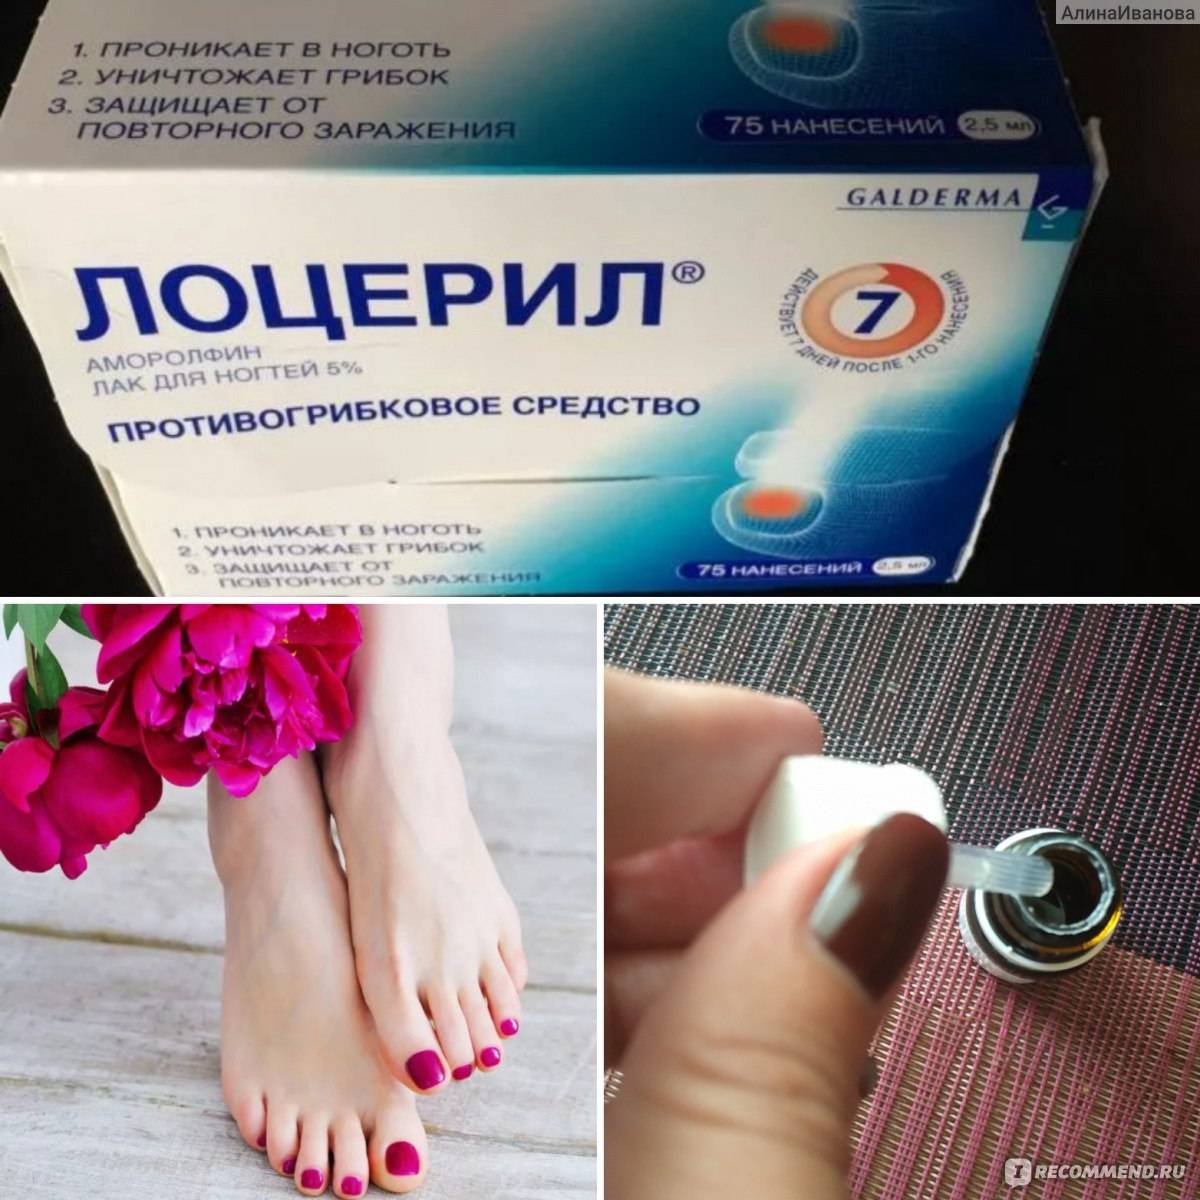

Механизмы действия антимикотиков: схемы и изображения